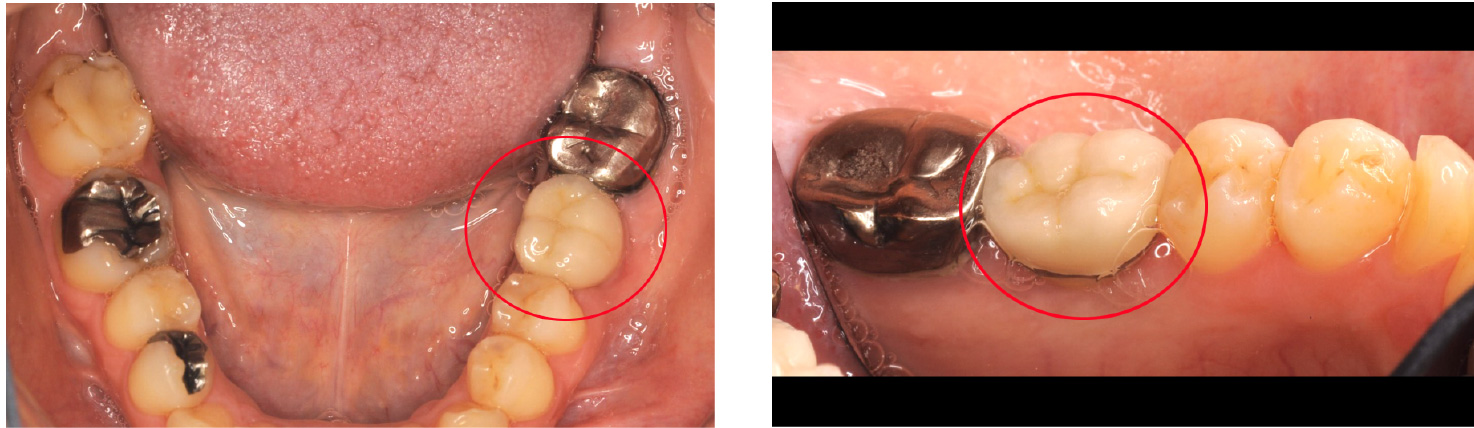

【インプラント埋入直後】

2009年6月当時67歳

2009年6月当時

【16年後】

2025年4月83歳

- 歯を失った右下部分にインプラントを2本埋入し、連結した被せ物(ブリッジ)で噛み合わせを回復しました。